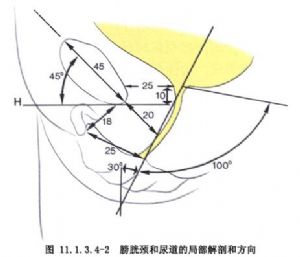

發生應力性尿失禁的原因約有:①位於膀胱頸部的內括約肌中兩組U字形平滑肌束,不能分別向尿道前、後收縮,因而關閉不住尿道;②外括約肌的橫紋肌層,在尿道中1/3段形成環狀括約肌,於膀胱內壓力升高時,不能增加張力,尿液即溢出;③肌肉,如恥尾肌、球海綿體肌;筋膜,如恥骨-膀胱-宮頸筋膜等,能保持膀胱和尿道的正常位置。如分娩損傷,肌肉及筋膜鬆弛,膀胱頸部脫垂,呈漏斗狀,易致應力性尿失禁;④正常時尿道後壁與膀胱三角底部呈90°~100°的鈍角,稱尿道后角。如膀胱、尿道周圍的肌肉、筋膜損傷、鬆弛,使尿道后角消失,這是尿失禁的重要原因(圖11.1.3.4-1~11.1.3.4-6)。

5.尿道膀胱造影,如發現尿道后角呈90°~100°而有尿失禁。重症時尿道與正中垂直線的角度增大,正常僅30°。